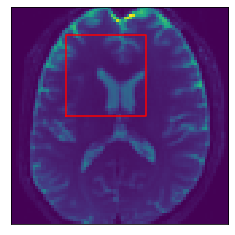

Inference stage. Now we present results of the inference stage with two DW-MRI real datasets. First, the free access dataset Stanford HARDI (Rokem et al., 2015) included in DIPY Library, with dimension (81,106,76) voxels and 160 signals per voxel (number of gradients). The acquisition protocol composed uses 150150150 gradients with b-value equal 200020002000 and 101010 with b-value equal zero. Second, a local DW-MRI with (128,128,70)12812870\left(128,128,70\right) voxels with 646464 gradients with b-value 100010001000 plus 111 gradient with b-value 00, each of them is repeated 555 times resulting in signals of size 325325325. Training time for our models by depends on datasets: The Voxel model takes 1.24sec.1.24𝑠𝑒𝑐1.24sec. for the Stanford HARDI and 1.24sec.1.24𝑠𝑒𝑐1.24sec. for out local dataset. Meanwhile, Neighborhood model takes 1.91sec.1.91𝑠𝑒𝑐1.91sec. for the Stanford HARDI and 3.34sec.3.34𝑠𝑒𝑐3.34sec. for our local dataset. Prediction times are shown in Table 1. Figure 7 compares the final results in a Stanford dataset slice, showing the local detected structure with the studied models. More slices results are presented in Appendix C.

Appendix C Axonal structure estimated in real data

Refer to caption

(a) DW-MRI

(b) Slice Zoom

Figure 13: Example 2. Predicted intravoxel structure in real data.